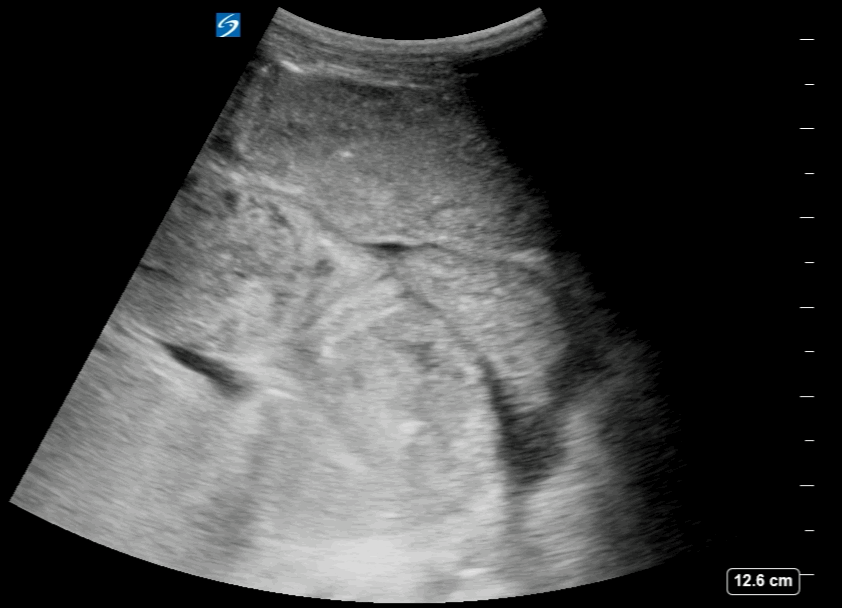

Free Fluid in between the Intestinal loops